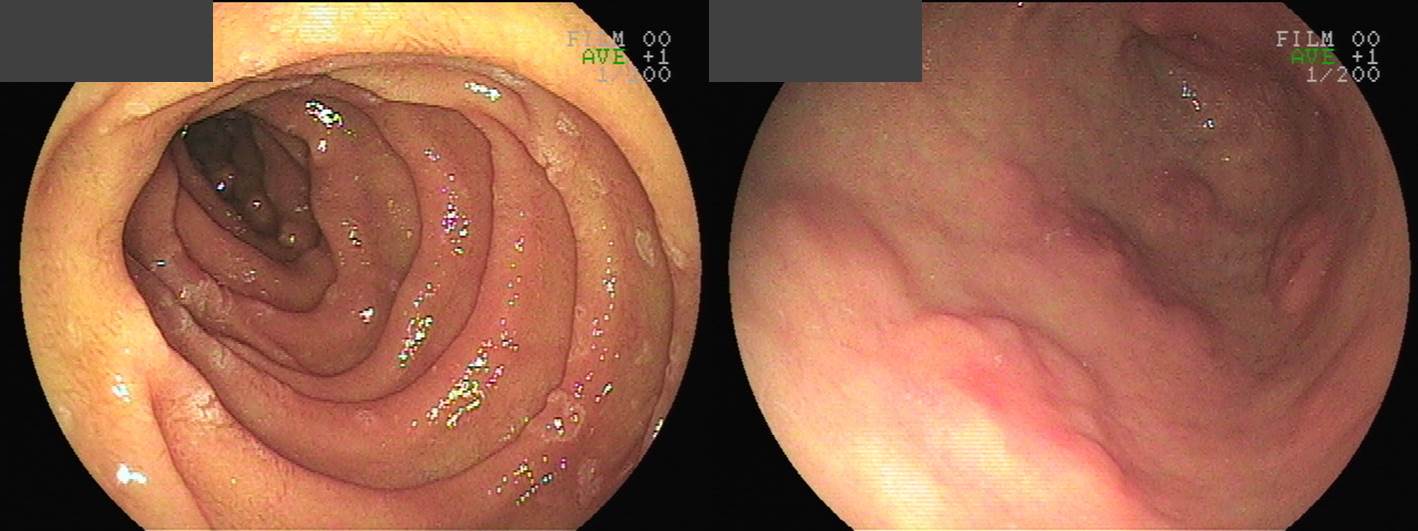

- ¼Ò°ß: Cecum°ú IC valve¿¡ ¼ö°³ÀÇ ¿ëÁ¾ÀÌ ÀÖ¾úÀ½. »óÇà°áÀåºÎÅÍ ÇÏÇà°áÀå±îÁö´Â ºñ±³Àû Á¤»ó Á¡¸· ÀÇ ¼Ò°ßÀ» º¸ÀÓ. AV 20cmºÎÅÍ Åõ¸íÇÑ º´º¯ÀÌ ¼ö½Ê°³ °üÂûµÇ¾úÀ¸¸ç(NBI¿¡¼´Â µµµå¶óÁ® º¸ÀÓ ), AV 10cmÀÌÇϷδ ¼ö½Ê°³ÀÇ ¿ëÁ¾ÀÌ °üÂûµÇ¾úÀ½.

- ³»½Ã°æ Áø´Ü: r/o attenuated FAP

- Âü°í: AV 20cm À§ÂÊÀ¸·Î´Â ´«¿¡ º¸ÀÌ´Â ¿ëÁ¾Àº ¸ðµÎ Á¦°Å ÇÏ¿´½À´Ï´Ù. AV 20cm ÀÌÇϺÎÀ§´Â º´º¯ÀÇ °¹¼ö°¡ ³Ê¹« ¸¹¾Æ Á¦°Å°¡ ºÒ°¡´É ÇÏ¿´½À´Ï´Ù. Anus Á÷»ó¹æÀÇ LST´Â Ç×¹®ÀÇ Á¤¸ÆÃѰú ³Ê¹« °¡±îÀÌ ÀÖ¾î, Á¶Á÷°Ë»ç È®ÀÎ ÈÄ Ä¡·á¿©ºÎ¸¦ °áÁ¤ÇÏ¸é µÇ°Ú½À´Ï´Ù.

¶Ç ´Ù¸¥ ȯÀÚÀÇ ´ëÀå³»½Ã°æ°ú ¼ö¼ú ¼Ò°ßÀÔ´Ï´Ù. ¿ëÁ¾ÀÌ µÇÁö ¾ÊÀº Á¡¸·¿¡¼µµ ¼±Á¾¼º º¯È°¡ ÀÖÀ½À» ¾Ë ¼ö ÀÖ½À´Ï´Ù.